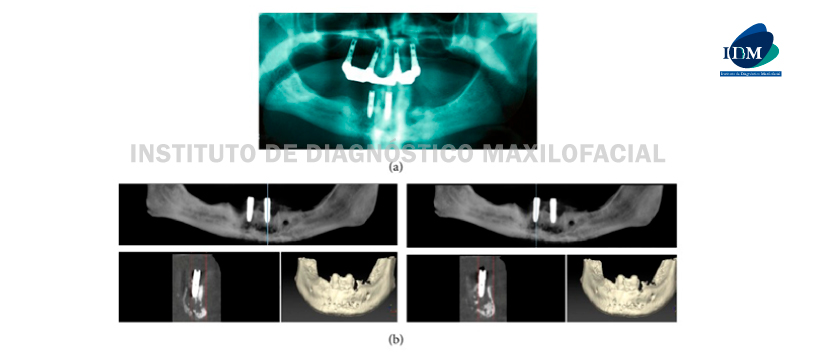

Una radiografía panorámica reveló una lesión osteolítica difusa radiotransparente con bordes mal definidos en el área de sínfisis de la mandíbula (Figura 3 (a)). La CBCT se realizó con urgencia para evaluar la lesión y reveló una osteólisis extensa, con destrucción de los bordes corticales en el área de los implantes. Los huesos alveolares y basales están afectados (Figura 3 (b)).